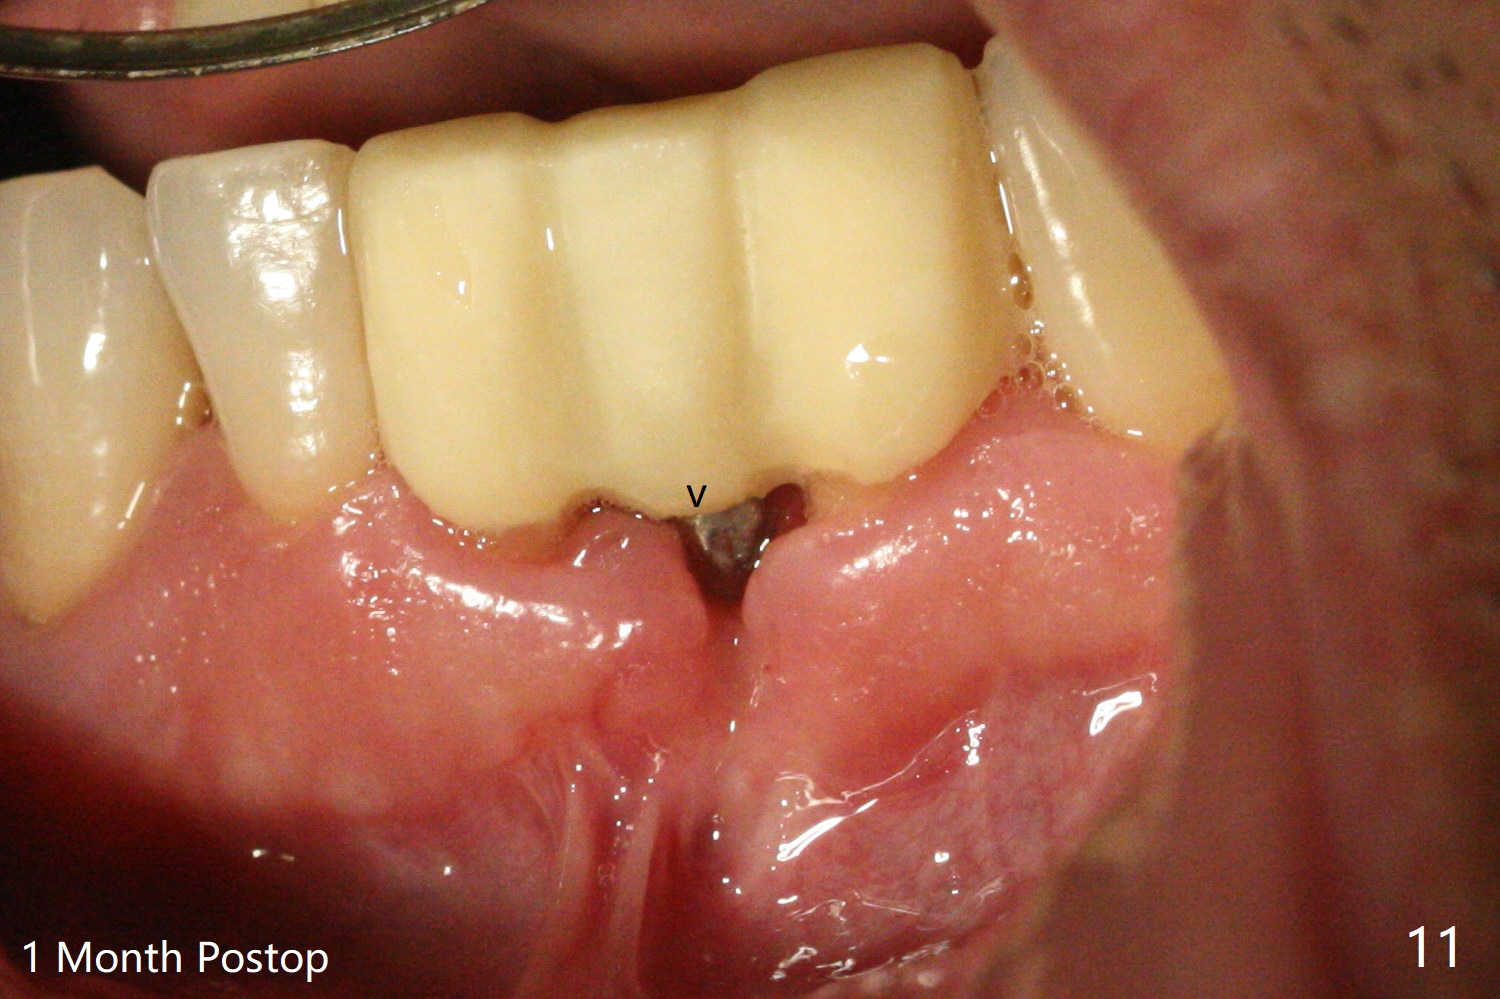

经过深洗以及改善口腔卫生,术前下前牙区牙龈基本没有红肿,但是缺牙处牙龈凹陷(图一,二:箭头),这个现象代表什么?如何影响手术进路?其实后者部分是因为牙龈与下面骨质(骨嵴)粘连(图三:*)产生的,分离粘骨膜瓣时不小心撕裂颊侧牙龈(图三(骨膜分离器下面:#),造成后来缝合困难,需要多用一个胎盘膜)。如果术前仔细分析CT 3D图像(图四,五)可以发现严重颊侧骨壁凹陷(图三:^)以及骨嵴(图四:*),事先抽血制备PRF膜和粘性骨粉,植骨效果好些(图六)。术中发现缺损,再抽血会拖延手术。最后将就用血调袢骨粉,使用胶原膜和胎盘膜覆盖(图七,八)。颊侧裂口术后十天愈合了(图九,十)。术后一个月颊侧牙龈凹陷,牙桥边缘(图十一:箭头)粗糙,临时牙桥取出,调整边缘,有利于局部卫生(图十二)。术后两个月桥边缘光滑(图十三:箭头),局部卫生和牙龈凹陷有所改善。病人将一个半月后回来取模。Return to Protect Graft 前磨牙即种 101 Xin Wei, DDS, PhD, MS 1st edition 04/30/2021, last revision 07/03/2021